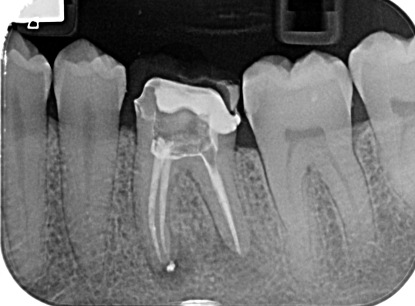

Il trattamento endodontico (devitalizzazione) consiste nel rimuovere la polpa dentaria o piu comunemente il nervo contenuto all’interno del dente e nelle sue radici, che sia infetto o infiammato.

L’obbiettivo di questa terapia è detergere, disinfettare e sigillare lo spazio lasciato libero dal nervo.

Attraverso l’esecuzione di una corretta terapia canalare si raggiunge l’obiettivo primario che è il mantenimento del dente, che dovra successivamente essere riabilitato protesicamente con corona o intarsio, all’interno del cavo orale scongiurando l’istaurarsi di infezioni e conseguentemente di dolore.

Il nostro Centro, in continuo aggiornamento e grazie all’utilizzo delle piu moderne tecnologie, è in grado di offrire elevati standard qualitativi del trattamento endodontico.